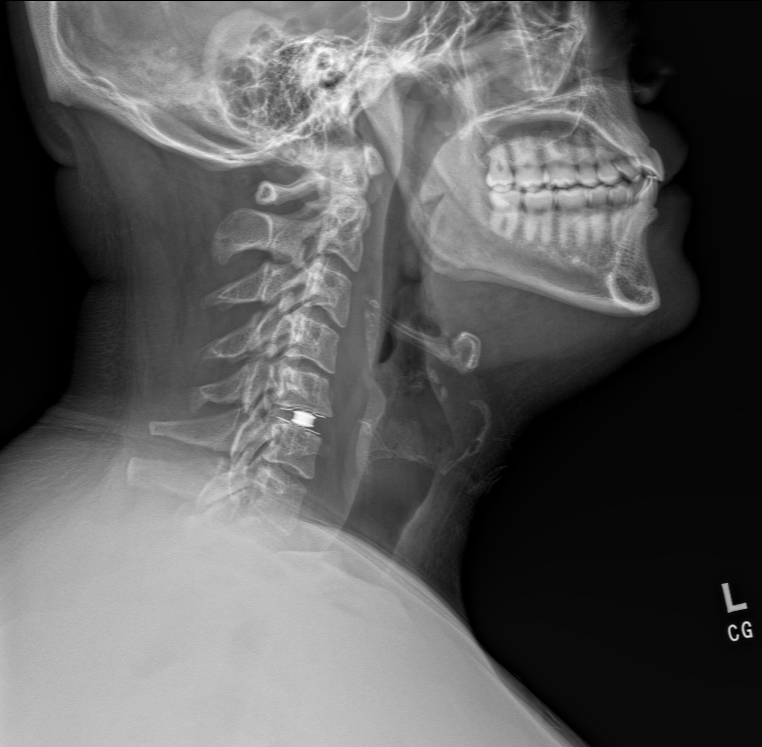

Anterior Cervical Disc Replacement